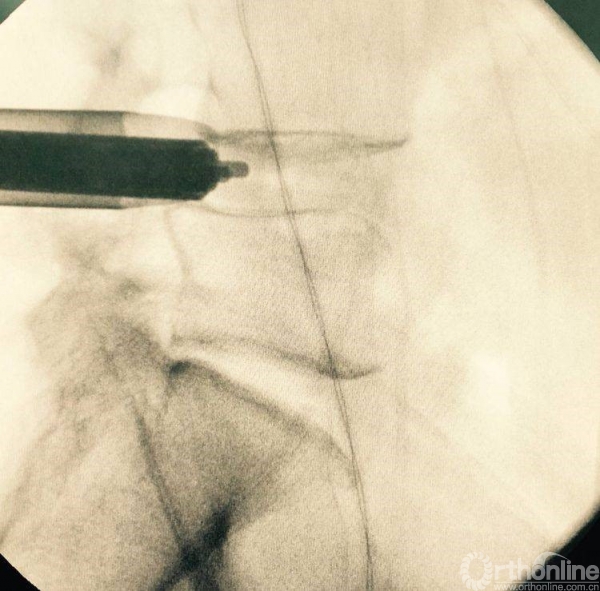

处理干净椎间隙后,透视观察工作通道的位置,镜下看到前纵韧带的纤维交错位置,为减压充分标志

正位观察透视,判断是否处理至边缘

12号试模决定融合器大小

充分植骨(关节成型时的自体骨质、也可配合异体骨使用),然后植入融合器,镜下观察融合器和硬膜囊位置并透视再次确认

正侧位透视观察滑脱是否复位、融合器及植骨的位置